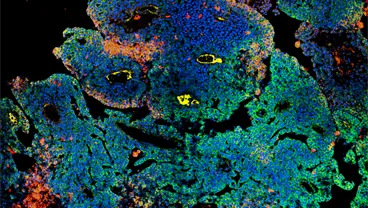

Cancer Biology and Imaging Group Our laboratory has adopted a multidisciplinary approach to devise a biomarker and model-driven…